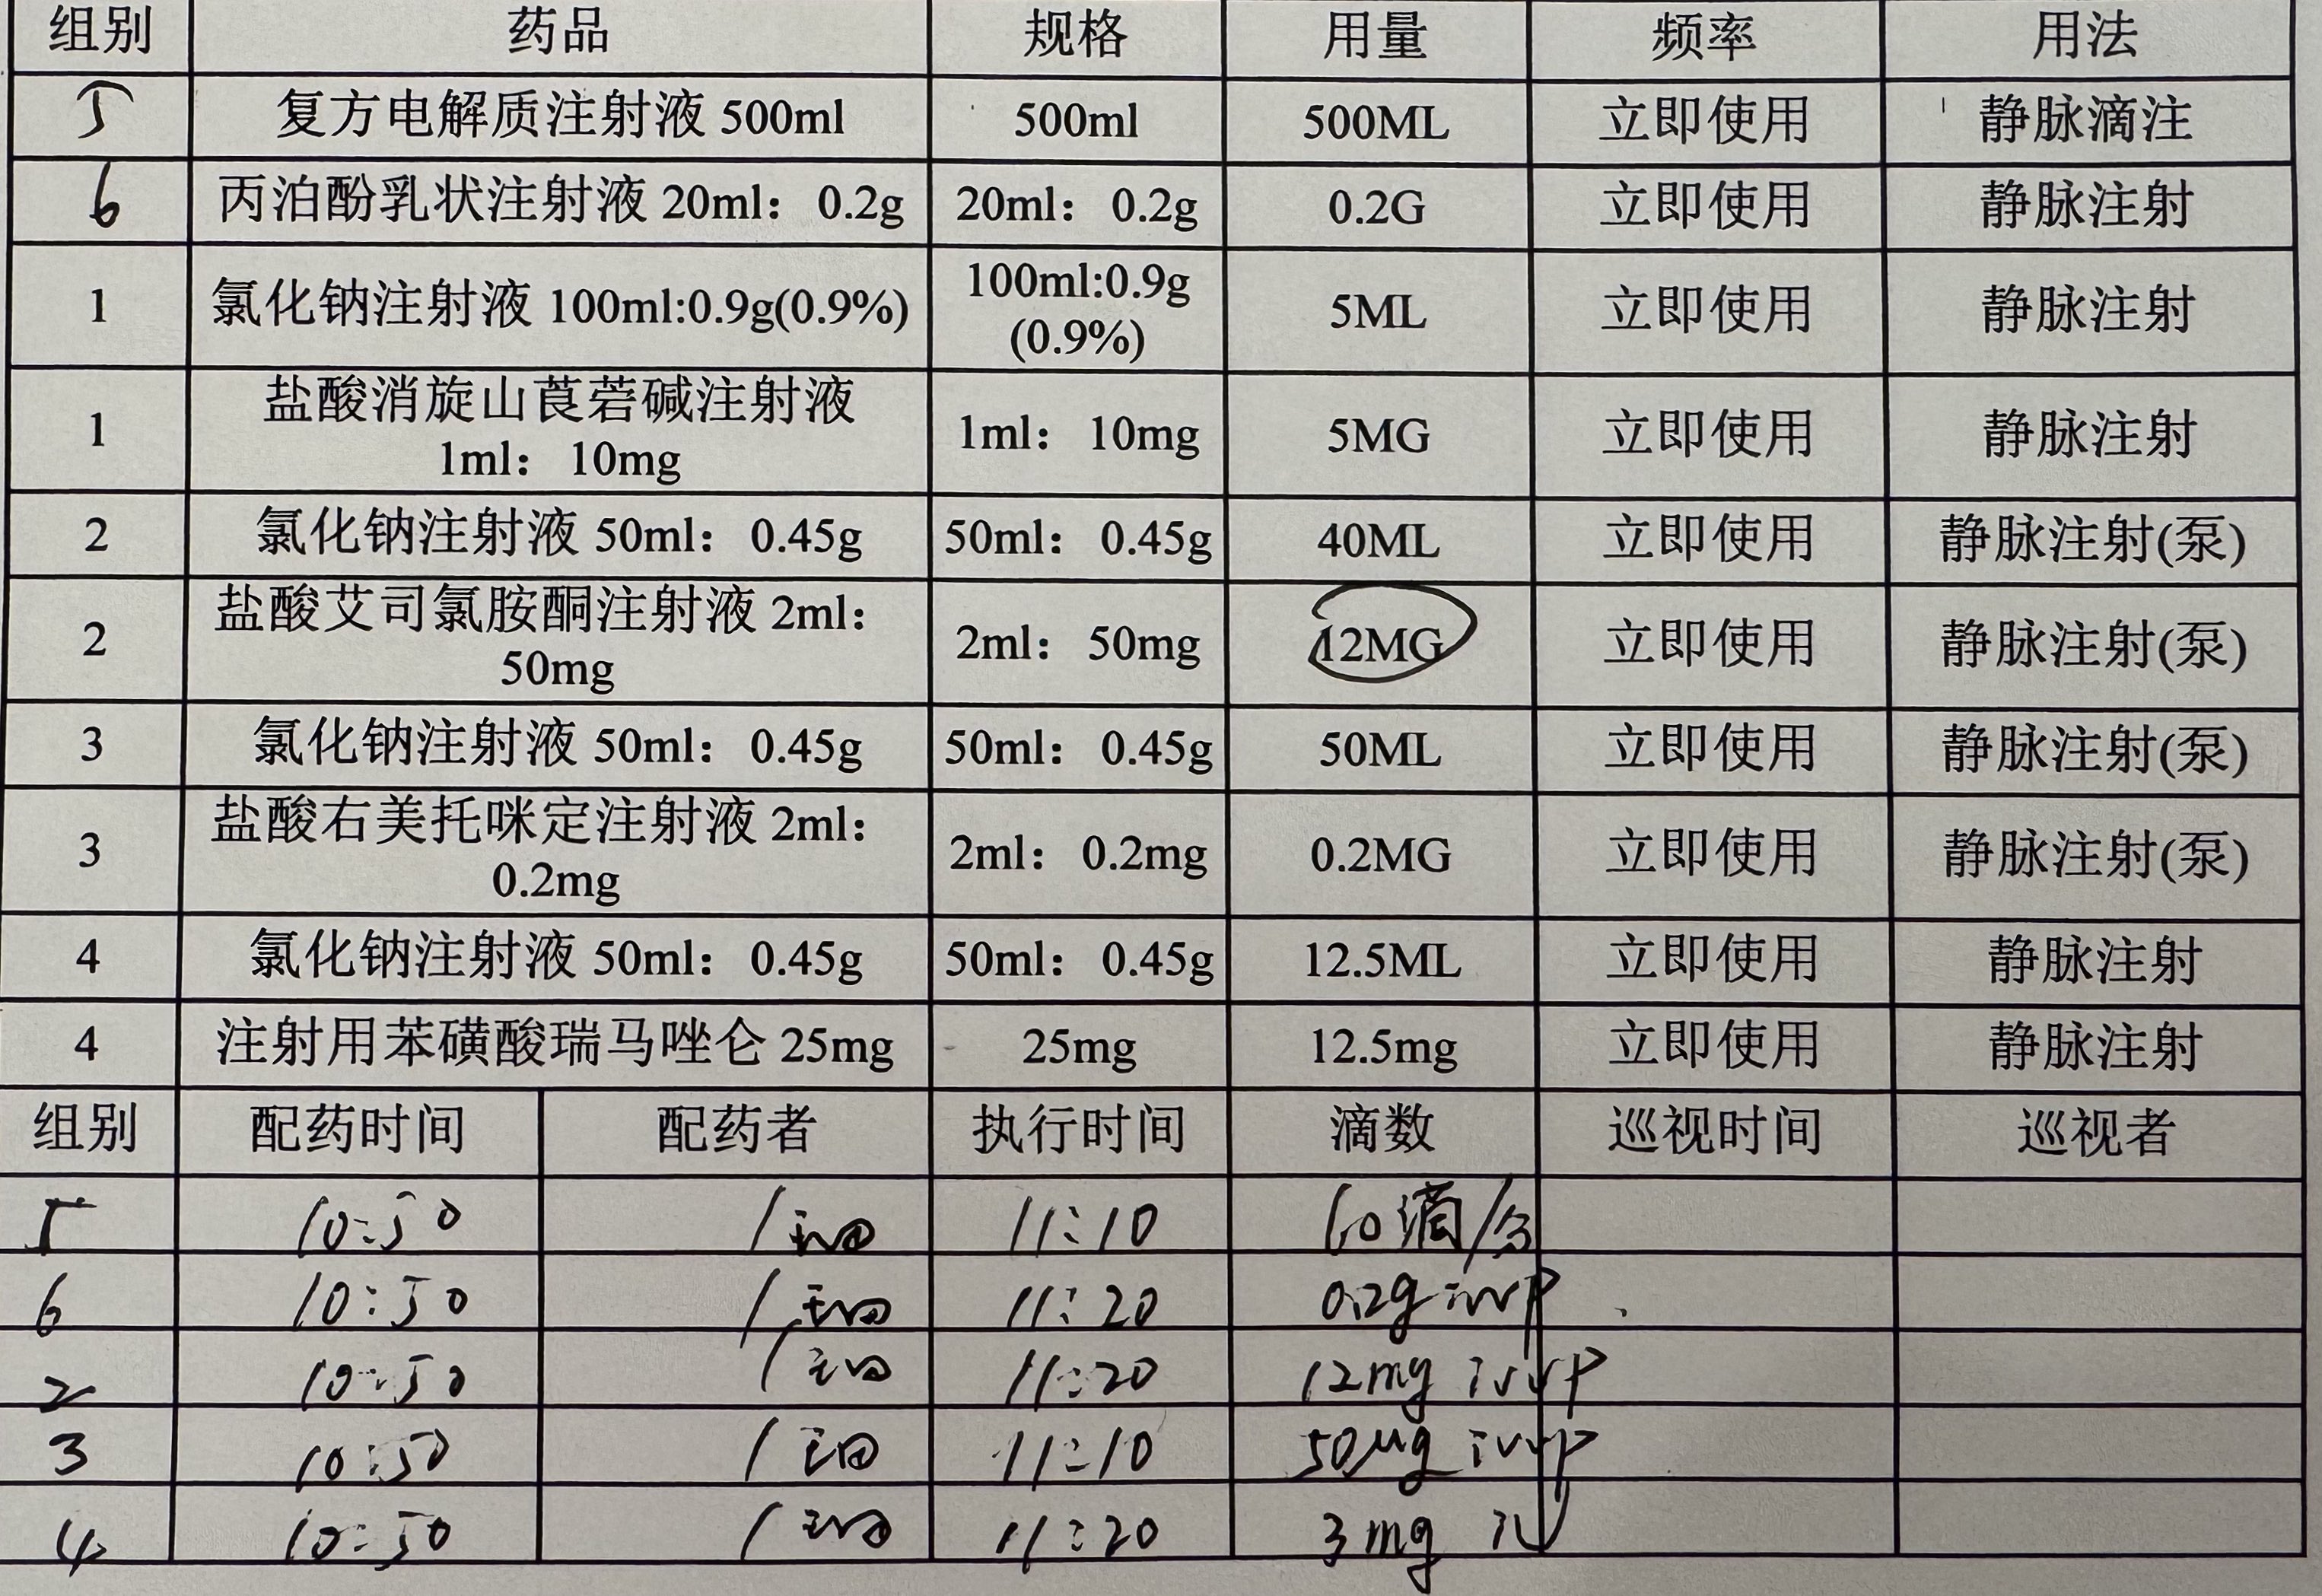

而临床处理药物中毒中,其实医生更常用的做法是保守、支持性的治疗,比如补液,促进代谢,必要时镇静,以及监测生命体征防治并发症。

而临床处理药物中毒中,其实医生更常用的做法是保守、支持性的治疗,比如补液,促进代谢,必要时镇静,以及检测生命体征防治并发症。